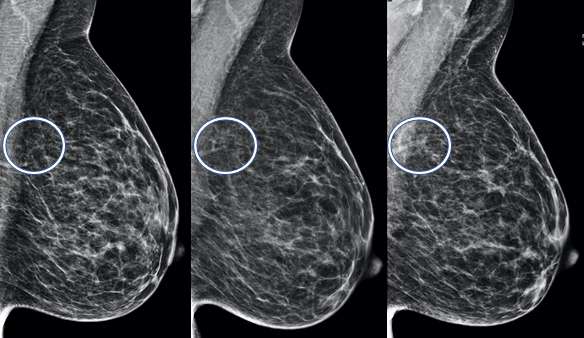

Developing Asymmetry:

A developing asymmetry is an asymmetry that is larger or more conspicuous compared to prior exams3. Since breast tissue tends to become less dense with age, developing asymmetries are usually more concerning and may warrant additional workup such as biopsies.